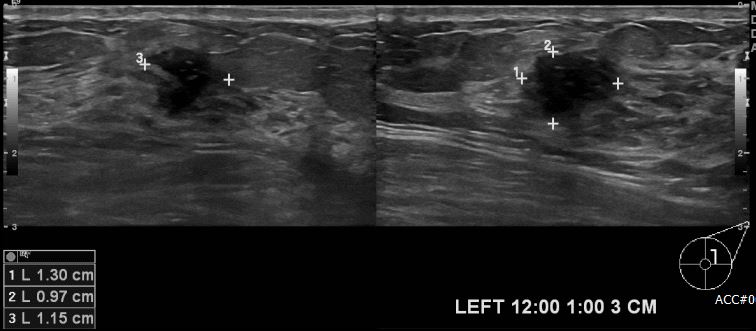

상기환자 좌측 유방에 만져지는 멍울로 내원하신 30대 여성분으로 좌측 12시~1시

방향에서 3cm 떨어진 거리에 만져지는 멍울 조직검사 시행하여 좌측 침윤성 유관암

진단되었습니다.